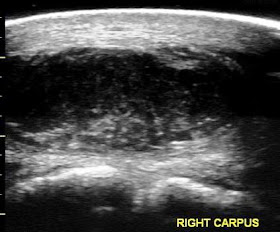

Several months ago I presented a case involving a gelding that presented for lameness and soft tissue swelling along the outside of the right knee (carpus). The gelding was lame at the walk and hesitant to flex the limb at the carpus. Ultrasound exam revealed a well demarcated soft tissue mass (dark tissue inside blue circle) that was centered over the carpus (Figures 1-3). The histopathology report was consistent with a fibrosarcoma.

The gelding's limb was evaluated 4 weeks after the second Cisplatin treatment. There was no evidence of the fibrosarcoma on the outside of the carpus AND under the skin (Figure 5). The ultrasound exam only noted normal subcutaneous tissue and joint capsule between the ultrasound probe and the carpus. The gelding was sound at the walk, trot, canter and has returned to full work!! The case is a good example of the benefits of intra-lesional injection of tumors that are non-operable with chemotherapy agents. There are several chemotherapy agents available and the procedure can be performed at the barn with ultrasound guidance.